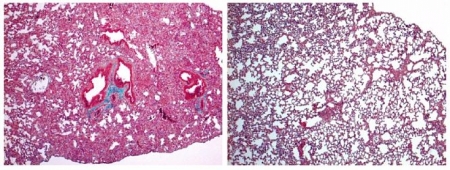

Un proyecto del CSIC identifica la cortistatina como estrategia "atractiva" para mejorar enfermedades hepáticas

Los investigadores han evaluado la capacidad de la cortistatina para regular la fibrosis hepática usando dos modelos experimentales